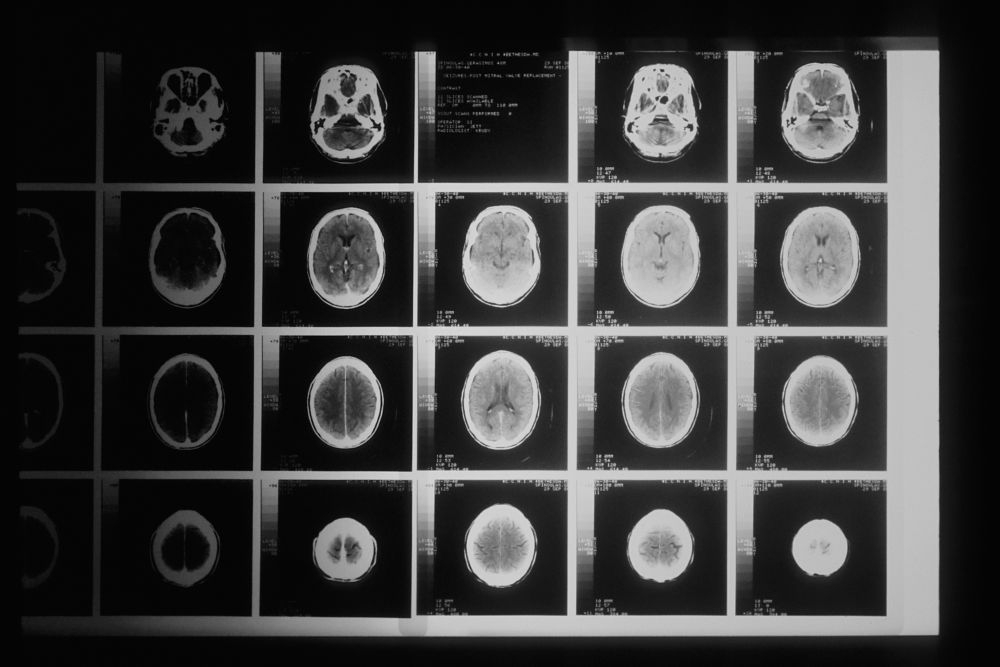

根據外媒報道,在英國的29歲媽媽Laura Elizabeth Mahon,在懷孕20周時突然發現腳趾不能動,當時沒有以為只是小毛病,怎料在隔日就感受不到右腳的存在,所以決定去求醫。一開始醫生以為是胎兒壓迫而引起神經問題,將她轉送另一間醫療中心進行磁力共振檢查。

經詳細檢查後,醫生證實她患了腦瘤,又指腦瘤可能已經存在很多年,直至現在才開始惡化。聽到這個消息後,Laura非常崩潰又指自己才29歲,沒有想過這種事情會發生在她身上。

Laura在去年底再次進行磁力共振檢查,發現腫瘤又增大了一倍,而且無法進行手術,主診醫生更告知她只剩下2年命,突如其來的消息震撼了Laura與Danny並作好最壞打算。